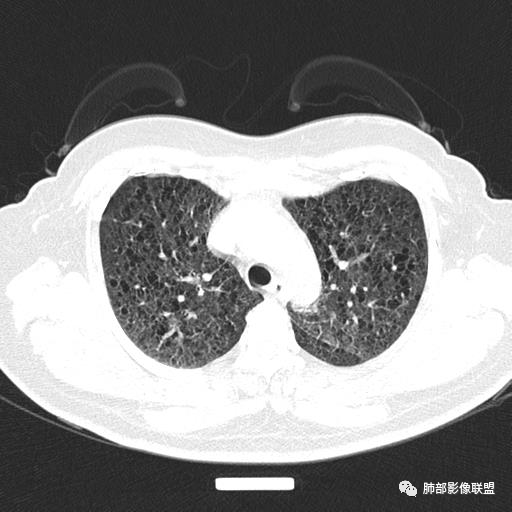

双肺弥漫囊腔,累及肋膈角,囊腔形态相对规则单一。

CT平扫示双肺弥漫分布大小不等囊状薄壁透光区,无内、中、外带分布差异,间质稍示增厚。拟LAM

中年女性育龄期妇女,咳嗽气喘,无吸烟史,有苯吸入史。影像:双肺弥漫均匀小囊腔,无明显分布优势,囊腔形态欠规则,壁薄,部分囊腔边缘血管征,伴双肺弥漫磨玻璃影,无结节,考虑lam,鉴别苯中毒肺损伤,囊腔多有分布优势,小叶中心分布为主,形态规整等

CT表现:双肺弥漫大小不等的薄壁囊腔,囊壁<2mm,外形规则,血管影多位于囊腔周围,囊腔之间肺组织正常,随着疾病进展到晚期,囊腔变大、增多,不可胜数,囊腔可融合成较大的囊,与肺气肿相似,形成间质性肺纤维化。部分病例可出现结节影。